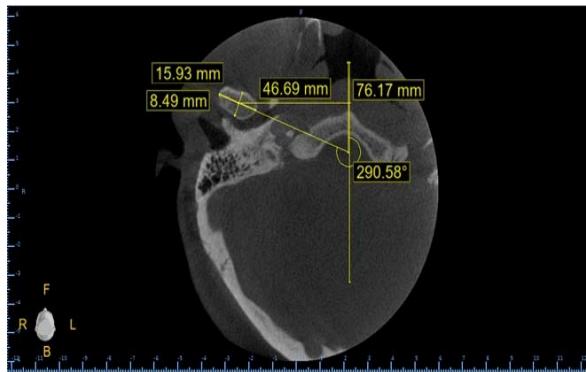

In the axial section, the measurements analyzed (MA) were (FIGURE 2):

1. Largest anterosuperior diameter of the condylar process of the mandible.

2. Largest mediolateral diameter of the condylar process of the mandible.

3. Angle between the long axial axis of the mandibular condyle and the median sagittal plane.

4. Distance between the geometric center of the condylar process and the median sagittal plane: measured by a line running from the geometric center of the condyle perpendicular to the median sagittal plane.

Figure 2: Illustration of axial cut measurements

Figure 4: Axial cut measurements